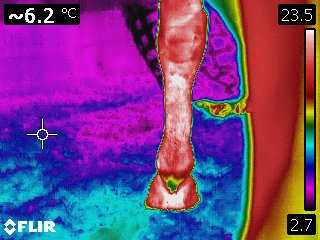

Infrared thermography is a dynamic modality providing a detailed, real-time image of the physiology of an area. It also provides an evaluation of the intensity and distribution of the heat associated with a tendon or ligament. As such, it is a method for specifically and repeatedly monitoring the extent of initial damage and to follow the repair process. Because thermography can accurately and repeatedly differentiate between various areas of tendon within a larger damaged area, sequential scans can provide useful information for treatment and in the repair process, as well.

Courtesy Kenneth Marcella, DVM

Courtesy Kenneth Marcella, DVM

Courtesy Kenneth Marcella, DVM